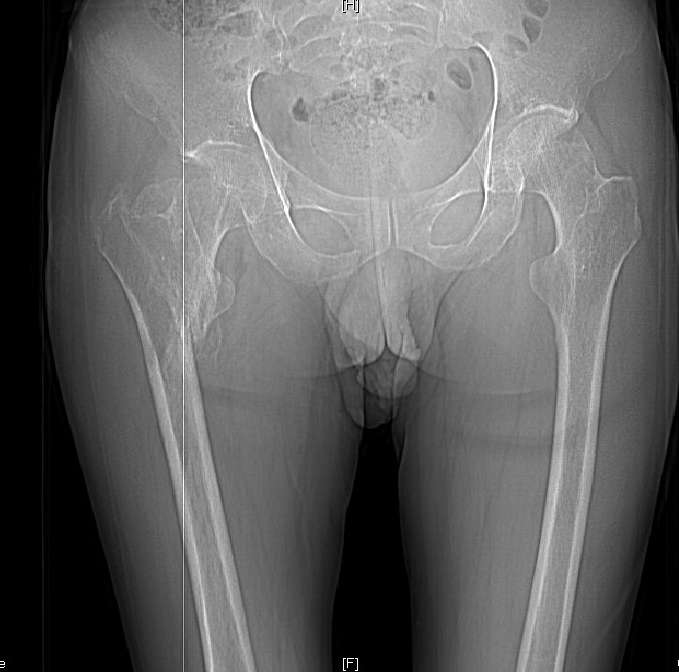

Доброго времени суток, уважаемые коллеги! Больному 45 лет. Лечили в сельской больнице на скелетном вытяжении 6 нед. по поводу межвертельного перелома бедренной кости с последующим наложением кокситной повязки еще на 2 мес.

С момента травмы прошло 5 месяцев, ходит с костылями без нагрузки, контрактуры в коленном и в тазобедренном суставах. Снимки во вложении. У нас мнения разделились. Показанием для открытого остеосинтеза мы считаем неустраненное ротационное смешение дистального фрагмента, которое может привести к нарушению биомеханики в тазобедренном суставе с последющими вытекающими последствиями. ЭОП на сегодняшний день недоступен нам, а остеосинтез угловыми пластинами, что можно попытаться, имеет определенный риск. Как быть? Начать разработку в суставах и активизировать больного, что не было сделано до этого, или всё-таки оперировать? Будем рады Вашим советам.

Никаких особенных проблем не видно, оперировать не видно, ради чего. Большого ротационного смещения нет, тазобедренный сустав - шаровидный, такие смещения прощает. Укорочение есть, но небольшое.

A что Вы думаете по поводу консолидации? Если имеется, почему до сих пор ходит с костылями? Если нет - о какой разработке суставов идет речь? Судя по рентгенограмме - не срослось. По КТ - ткань розового цвета между отломками такая же, как та, что покрывает головку. Тоже вроде не срослось. Мужику 45 лет. Конечно оперировать.